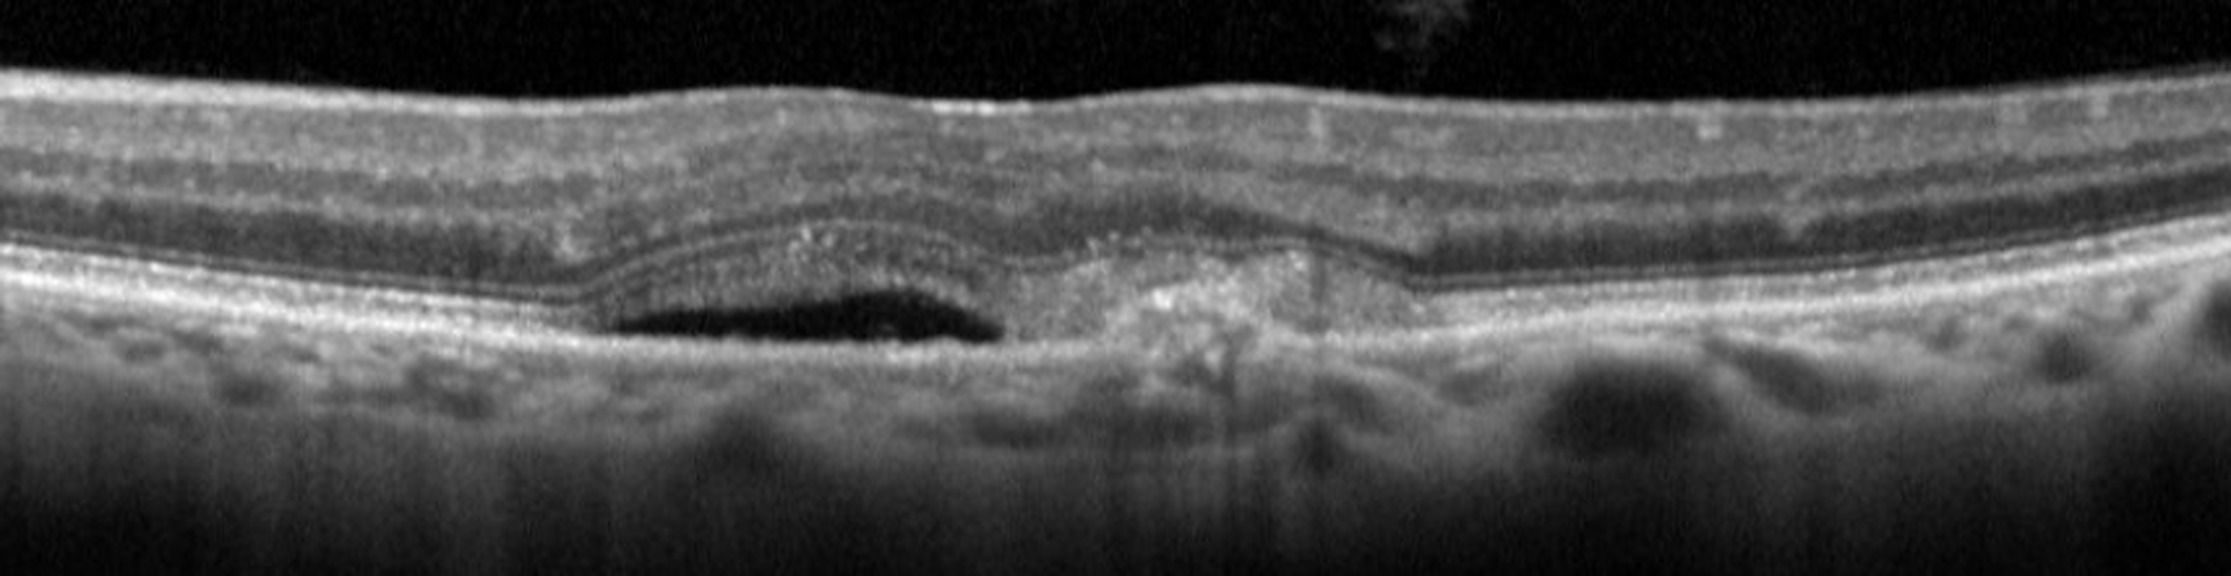

La réalisation d’une tomographie par cohérence optique OCT est rapide, indolore, non invasive et permet d’obtenir des résultats reproductibles. L’OCT est donc devenu un examen de routine incontournable dans le diagnostic et suivi des lésions liées à la DMLA. Les technologies récentes permettent de visualiser avec précision l’existence ces anomalies, de préciser également leur topographie et même de les quantifier.

L’OCT-Angiographie (OCT-A) est une technique d’imagerie rapide et récente qui s’accompagne d’une nouvelle sémiologie. Elle permet de mettre en évidence, d’une manière non invasive, le flux circulatoire des vaisseaux du fond d’œil et, de ce fait, les trajets vasculaires sans injection intraveineuse de colorant. La lecture et l’interprétation des flux sanguins sont très précises. L’OCT-A est devenu très utile pour éliminer ou mettre en évidence une activité néovasculaire.

Identifier les différentes lésions de la DMLA en OCT et OCT-A

Analyser les images en OCT et OCT-A pour le diagnostic et le suivi des patients DMLA